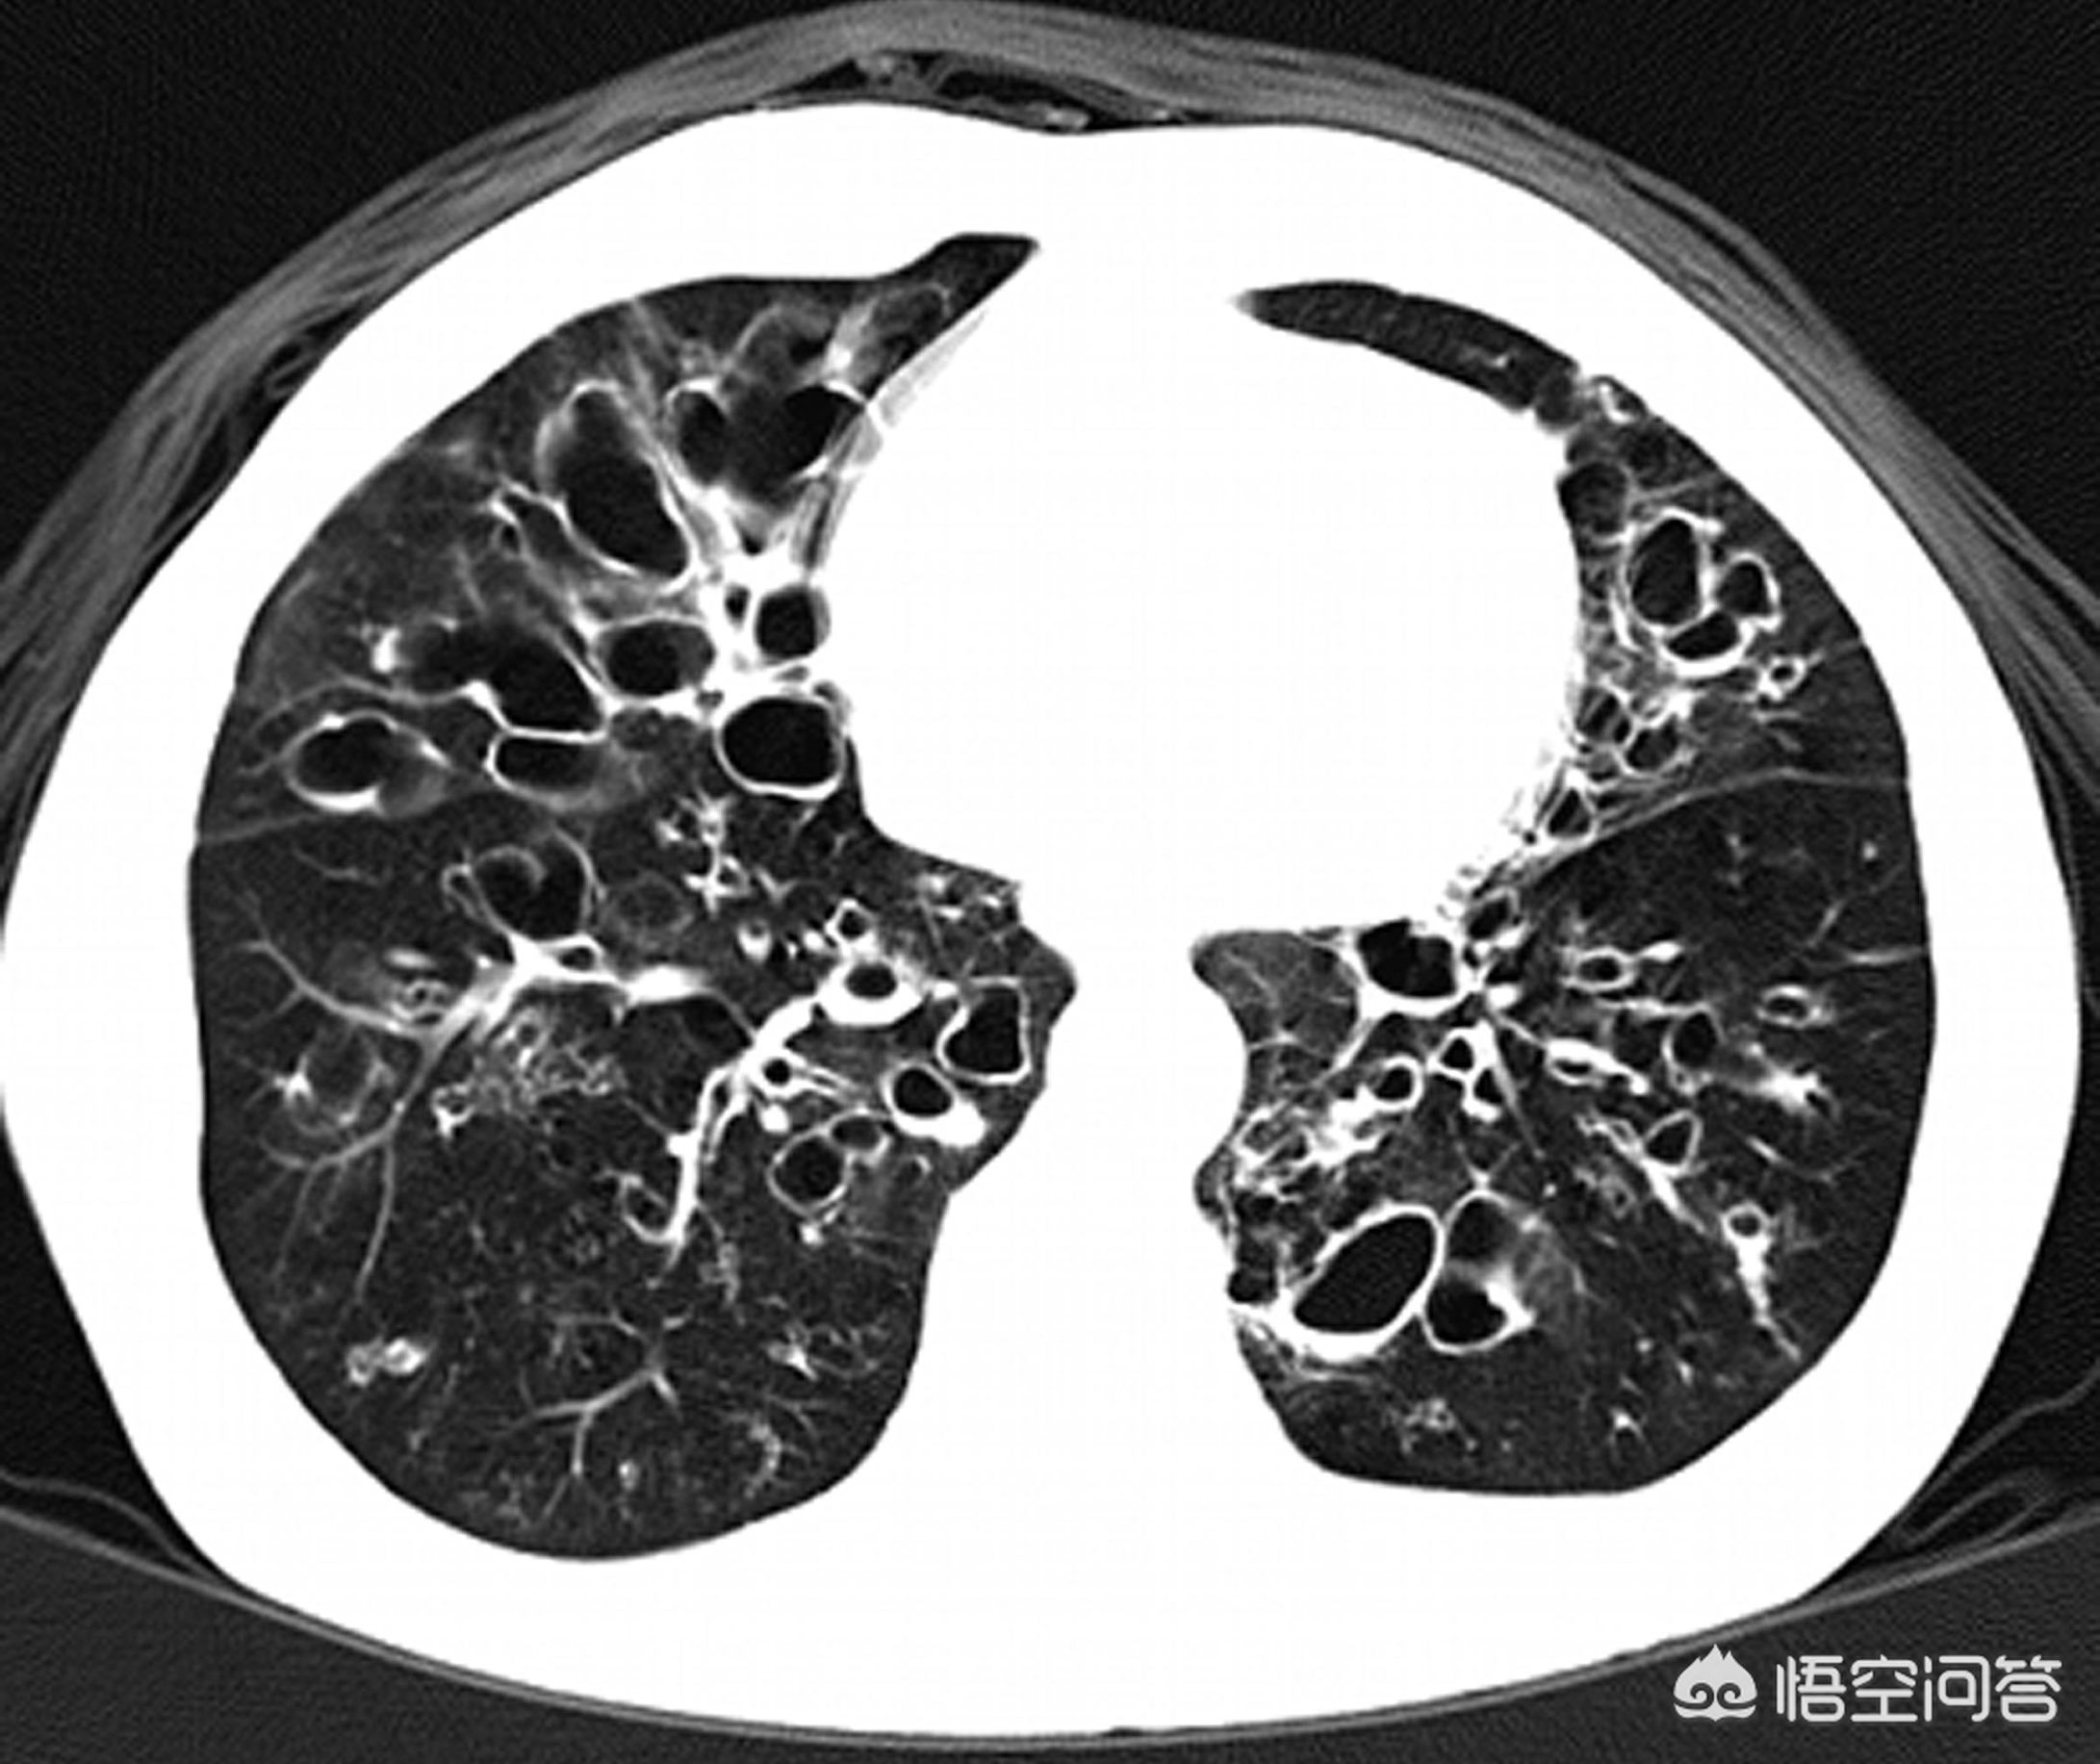

支气管扩张是一种结构破坏性疾病,通常是因为感染,有些是因为创伤,造成肺部特别是支气管管壁以及周围支撑组织损伤破坏而引起,还有一些是先天性疾病引起,比如纤毛不动综合征,幼年起就容易感冒咳嗽发热,逐渐形成支气管扩张,同时伴有特征性的内脏范围,不孕不育。支气管扩张分为局限性支扩和弥漫性支扩,局限性支扩相对症状较轻,可以通过手术根治,弥漫性支扩则症状持续,并进行性加重,只能通过药物等方法控制症状。

双下肺弥漫性支扩的患者则容易病情不断发展并且自我加重,这主要和痰液淤积不容易排出有关,支扩的患者管壁遭到破坏,局部免疫力随之崩塌,管壁表面的一些扮演搬运工角色的结构——纤毛不能正常工作,大家知道,气管壁表面细胞都长有头发也就是纤毛,这些纤毛可以向着咽喉部一起摆动,这样就能够把每天分泌的粘液排出,但支扩患者这方面功能受损导致粘液不断淤积,而肺又是和外界相通的,吸进来的细菌本应该被正常的免疫系统清除,在支扩患者身上则会迅速的定植到粘液中,并吸收粘液中丰富的蛋白质而生长形成感染并进一步破坏支气管,这就是支扩自我加重的原因。因为下肺支扩患者无法自我排出痰液所以必须借助于体位引流排痰,我之前多次科普过体位引流排痰的方法,经典的姿势是像青蛙一样趴在床上,头低屁股高家人帮忙拍背,将痰液缓慢咳出,每天十五分钟可以保持支扩病情稳定。